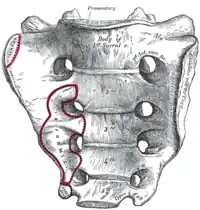

Cara lateral del sacro y coxis. Base del sacro.

Base del sacro. Corte sagital del sacro.

El borde anterior de S1 es sobresaliente y se denomina promontorio sacro. El vértice se articula con el cóccix. El orificio vertebral del sacro se denomina conducto sacro. Contiene las raíces nerviosas de la cola de caballo (raíces de nervios espinales situados debajo de L1). En las caras pélvicas y dorsal del sacro aparecen cuatro pares de orificios sacros a través de los cuales emergen ramos dorsales y ventrales de los nervios espinales.

Promontorio

El promontorio sacro marca la frontera de la entrada de la pelvis, y cuenta con la línea iliopectínea y línea terminal.[4] El promontorio sacro se articula con la última vértebra lumbar para formar el ángulo sacrovertebral, un ángulo de 30 grados con respecto al plano horizontal que proporciona un marcador útil para un procedimiento de implante cabestrillo.